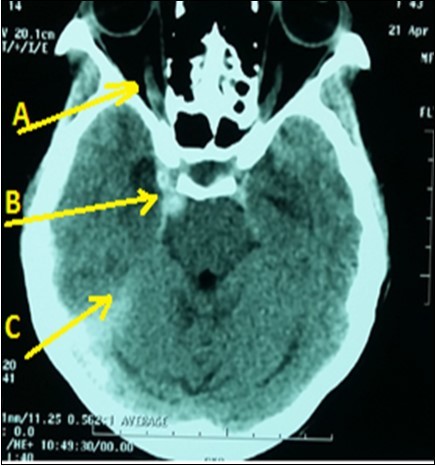

A 43-year lady, right-handed, single and mother of two children, was admitted in emergency neurology for intense headaches with vomiting, 2 generalized seizures and a sudden onset of consciousness disorders on April 19, 2016. Symptoms began two hours before her admission. She had no vascular history. The physical examination revealed intense headaches. The blood pressure was 130/80 mmHg with normal temperature (36.8 ° C). There was a light comas status with a Glasgow score of 12/15, a stiff neck, left hemiparesis and a bilateral Babinski reflex, right ptosis associated with reactive mydriasis, an exophthalmos and a total right ophthalmoplegia. Ophthalmologic examination revealed a right visual acuity of 1/10 with macular chorioretinitis. The brain CT scan (Figure 1) displayed a dilatation and hyper-density of right cavernous sinus with dilatation of the right ophthalmic vein associated with a subarachnoid hemorrhage. The routine biological tests were normal. An analgesic treatment had been administered in addition to nimodipine and mannitol (against brain edema) and clonasepam (against seizures). Unfortunately, as interventional neuroradiology and arteriography are not available, the patient had died on the seventh day of hospitalization in a context of increased intracranial hypertension.

Figure 1.Brain CT scan displaying right CCF (Arrow B) with subarachnoid hemorrhage (Arrow C) and right ophtalmic vein dilatation (Arrow A)